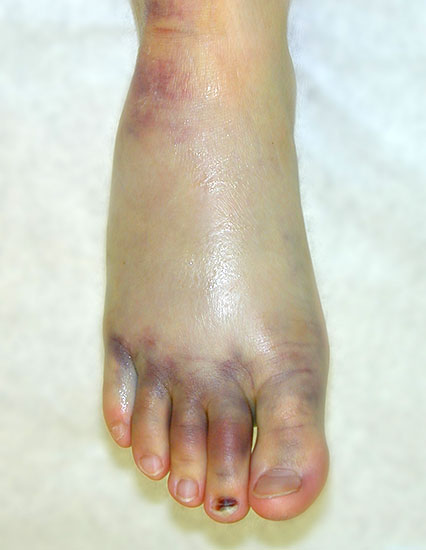

Röntgenaufnahmen dienen vor allem zum Ausschluss einer knöchernen Verletzung und umfassen Aufnahmen des Sprunggelenks anterior-posterior, lateral und 20° Innenrotation (Mortise view). Die über viele Jahre empfohlenen gehaltenen Aufnahmen haben ihre Bedeutung bei der Akutverletzung vollständig verloren, da sie die Behandlungsstrategie nicht beeinflussen (Abb. 2). Bei einer chronischen Instabilität liefen gehaltene Aufnahmen zusätzliche Informationen, wobei auch hier falsch negative Befunde möglich sind 26. Die höchste Zuverlässigkeit liefert die dynamische Untersuchung in Narkose 27